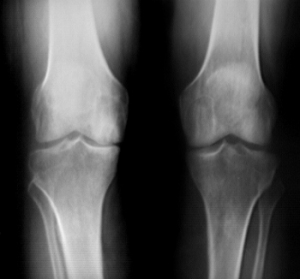

Radiological Testing

X-rays can help in the diagnosis and may be the only special test required in the majority of cases. X-rays can also help doctors rule out other problems, since knee pain from OA may be confused with other common causes of knee pain, such as a torn meniscus or kneecap problems. In some cases of early OA, X-rays may not show the expected changes.